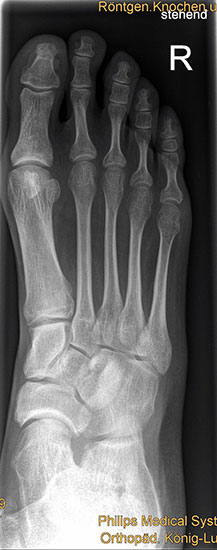

Die Standardröntgendiagnostik bei Fußfehlstellungen und asymmetrischen Arthrosen besteht in stehenden Aufnahmen des Fußes in 2 Ebenen (dorsoplantar und lateral), sowie einer stehenden ap Aufnahme des Sprunggelenks und eine „hindfoot alignment view“ nach Saltzman, mit der die inframalleoläre Rückfußachse beurteilt werden kann 7. Ganzbeinstandaufnahmen sind essentiell, um die mechanische Achse der gesamten unteren Extremität zu analysieren. Zur genauen Analyse des Knorpelzustands bietet sich die Kernspintomographie an. Für spezielle Indikationen steht das SPECT-CT zur Verfügung.